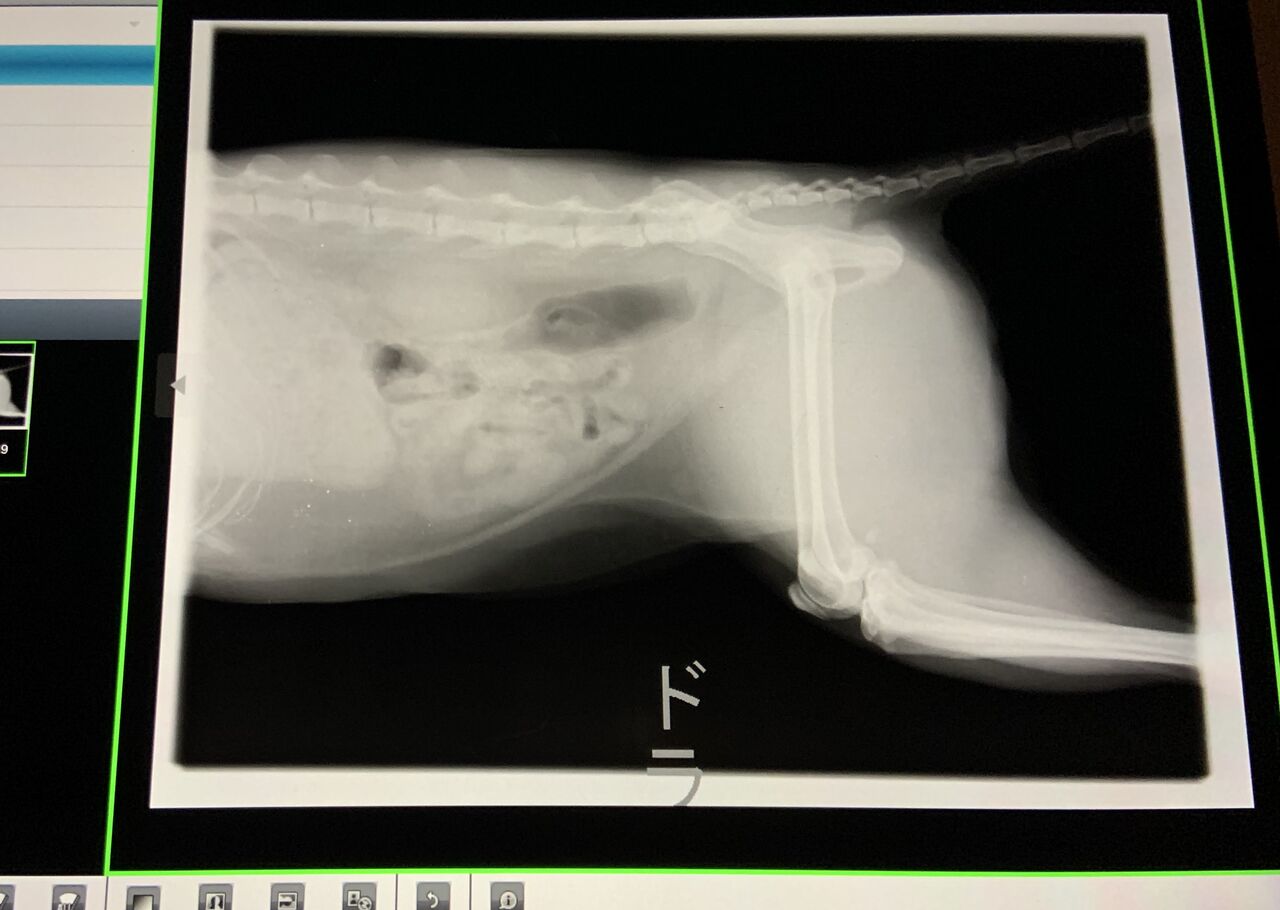

エコーとレントゲンの結果、尿管閉塞を起こすような石はできていないことが

確認できたので、少し安心しました

▼レントゲン